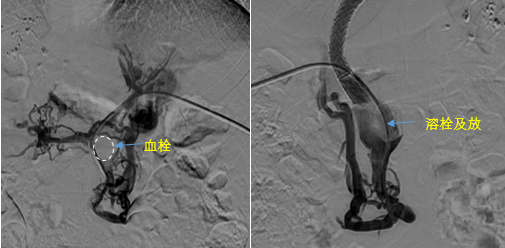

在西安國際醫(yī)學中心醫(yī)院,韓國宏教授對李女士進行了細致的問診及檢查,在CT圖像上仔細的分析,針對患者特殊的病情制定了詳細的治療方案。第一次進入手術室,在DSA的監(jiān)測下,造影過程中門靜脈血栓的輪廓逐漸顯現(xiàn)出來,見多識廣的醫(yī)生們也大吃一驚,發(fā)現(xiàn)遠端脾靜脈及腸系膜上靜脈也存在大量血栓?;颊叩氖彻芪傅嘴o脈曲張非常嚴重,疏通堵塞的門靜脈已是刻不容緩。

見此情形,韓國宏教授憑借豐富的臨床經(jīng)驗很快調(diào)整了策略,在超聲診療中心的協(xié)助下進行門靜脈右支穿刺,并進行造影,看到目標血管后,韓國宏教授用“明修棧道,暗渡陳倉”的方法,讓來自脾臟和胃腸的血流終于暢通的回流到了肝靜脈。通過血流的沖刷以及抗凝溶栓藥物的作用,幾日后復查造影發(fā)現(xiàn)門靜脈血栓已逐漸變小,不會對回流到肝臟的血流產(chǎn)生大的阻礙作用,門靜脈的壓力顯著減小,患者再次出血的幾率也隨之降低。幾經(jīng)周折,這顆“定時炸彈”終于被拆除,李女士和她的家人多年來心里的石頭也終于落地。